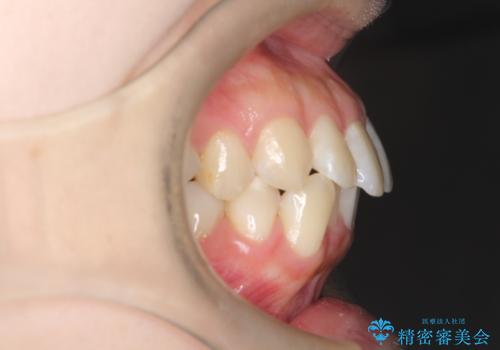

- 口元をさげたいという主訴で来院されました。4番の歯を4本抜歯し、審美装置にて治療をしました。

抜歯をしたことで口元の突出感が改善しました。約2年を予定していた矯正ですが、約1年という短い期間で終了できました。